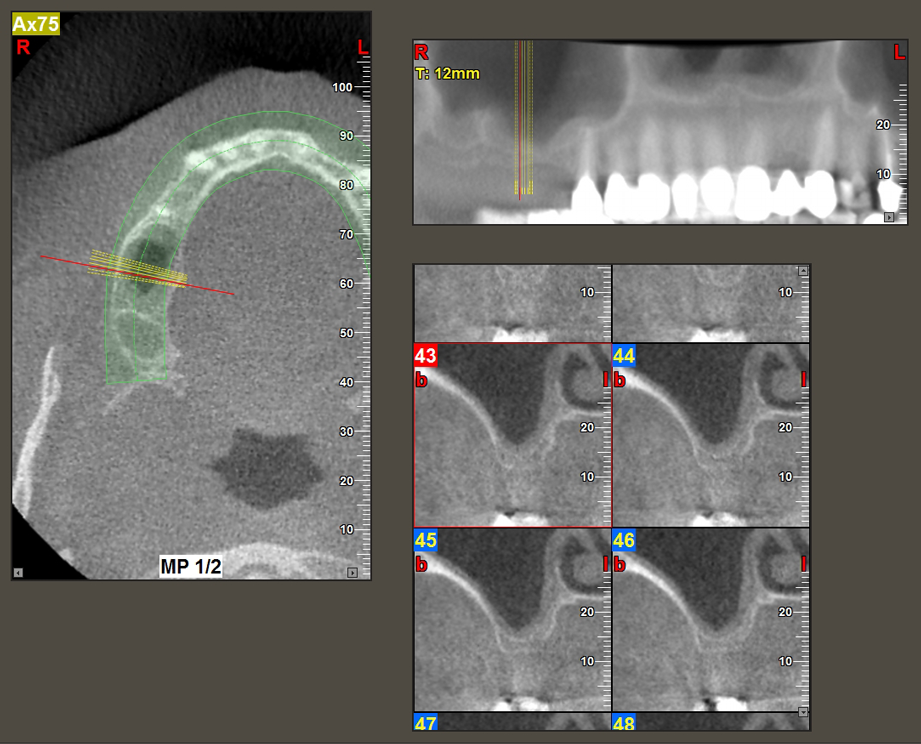

A 49-year-old female patient, a non-smoker and with nothing remarkable in her general medical history, was referred to our oral surgery practice for surgical extraction of tooth 16 and subsequent implantation. After the extraction, the patient experienced mild sinusitis trouble with the resultthat we initially waited six months before carrying out the measure. The residual bone height at the planned implant position measured 3-4 mm (Fig. 1 and 2).

The I2A instrument (diameter 2.0 mm) was then used to perforate the sinus floor intermittently and on the smallest scale possible. This special piezosurgical method ensures that the Schneiderian membrane is not damaged. When the Z25P was used, the membrane was already lifted slightly by the coolant supplied via the instrument tip (Fig. 3). The coolant quantity was just 50% in order to avoid high pressure in the implant bed.

Implant bed preparation and augmentation

Following an intermediate check (Fig. 4) a further preparation step was performed (Fig. 5). Afterwards, the hydraulic Z35P instrument was used to lift the membrane to the desired position (Fig. 6 and 7). This was followed by further piezosurgical preparation of the implant bed, concluded with a rotary bur and shoulder milling cutter up to the implant diameter of 4.8 mm. Before the implant was inserted, the augmentation material (particle size approx. 0.8-1.6 mm) was introduced underneath the Schneiderian membrane (Fig. 8).